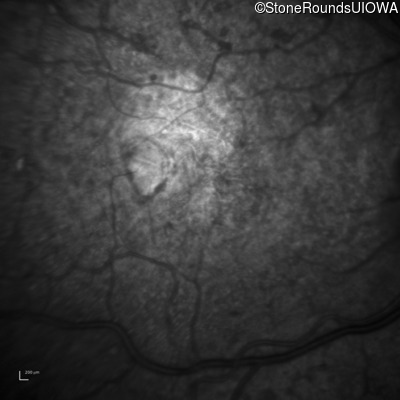

Infrared Fundus Photograph - Right - 20/1000 sc

Exemplar